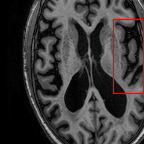

Sparsity Ikzsubscriptsuperscript𝐼𝑧absent𝑘I^{z}_{\downarrow k} LI 2D CNN 3D CNN Ours GT Ikz+1subscriptsuperscript𝐼𝑧1absent𝑘I^{z+1}_{\downarrow k}

Refer to caption Refer to caption (a) 27.37/0.8465 Refer to caption (b) 32.34/0.9441 Refer to caption (c) 32.72/0.9436 Refer to caption (d) 34.11/0.9607 Refer to caption (e) PSNR(dB)/SSIM Refer to caption

8 Refer to caption Refer to caption Refer to caption Refer to caption Refer to caption Refer to caption Refer to caption

Refer to caption Refer to caption (f) 25.51/0.7681 Refer to caption (g) 28.29/0.8205 Refer to caption (h) 29.51/0.8824 Refer to caption (i) 31.87/0.9249 Refer to caption (j) PSNR(dB)/SSIM Refer to caption

Figure 5: Visual comparisons of slice interpolation approaches. For 4x sparsity, the second of three interpolated MR slices is presented. For 8x sparsity, the third of seven interpolated slices is presented.

In Fig. 5, we present the observed slices Ikzsuperscriptsubscript𝐼absent𝑘𝑧I_{\downarrow k}^{z} and Ikz+1superscriptsubscript𝐼absent𝑘𝑧1I_{\downarrow k}^{z+1} along with the interpolated slices produced by different methods. Specifically we demonstrate the second of three interpolated MR slices for 4x sparsity, and the third of seven interpolated slices for 8x sparsity. We highlight the region where the anatomical structures significantly change compared to the observed slices Ikzsubscriptsuperscript𝐼𝑧absent𝑘I^{z}_{\downarrow k} and Ikz+1subscriptsuperscript𝐼𝑧1absent𝑘I^{z+1}_{\downarrow k}. We observe that although 2D CNN has comparable performance in terms of PSNR and SSIM, it tends to produce false anatomical structures in the zoomed regions. 3D CNN is able to resolve more accurate details. However, the improvement is quite limited, which we attribute to the fact that 3D CNN requires more training MR volumes in order to generalize and has smaller receptive field due to patch-based training. Our method benefits from the large receptive field of 2D CNN and two-view fusion, which not only produces sharper images, but also correctly estimates brain anatomy. The sharp and accurate estimation is crucial in clinical applications such as diagnosing Alzheimer’s Disease by brain volume estimation.